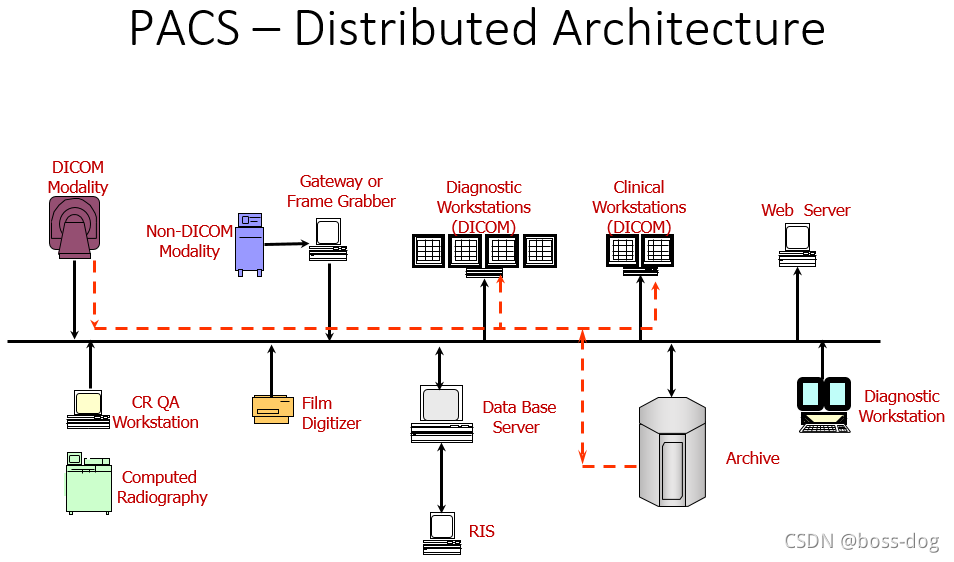

PACS分为两种:一种是图像的服务器为中心(PACS – Central Architecture),还有一种是分布式的(PACS – Distributed Architecture)。

PACS – Distributed Architecture的优缺点:

优点:比如MR扫描出来的图像就直接到了临床医生或者放射科医生的面前,就不需要第三方的服务器;如果服务器坏了,也不影响整个系统。

缺点:需要复杂的路由算法;如果大家都需要同时看一些图,那么分布式的结构就由一定的困难。

- PACS系统的组成:

HIS/ RIS(关于病人的信息、预约信息)

Broker(代理)

ePR gateway(网关)

Database Server(数据库)

Image Server (RAID)(图像数据库)

Long Term/ Near line Archive(长期、近期的档案整理)

Networks(网络)

Digitizer(数字化处理)

Acquisition Gateways(采集网关)

Non-DICOM modality gateway(非DICOM格式图像的处理)

DICOM Print Server(需要连接胶片打印机)

Media Server(拷刻成光盘)

Reporting Server(形成意见报告)

Monitor QC Server(和显示器的连接)

Web Server(Web服务端)

Workstations(给医生看图片的工作站)